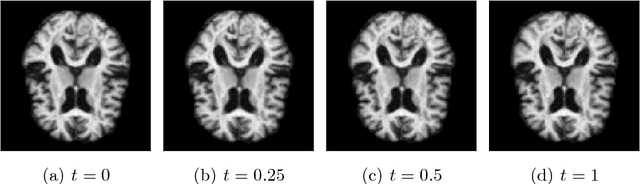

Abstract:Matching of images and analysis of shape differences is traditionally pursued by energy minimization of paths of deformations acting to match the shape objects. In the Large Deformation Diffeomorphic Metric Mapping (LDDMM) framework, iterative gradient descents on the matching functional lead to matching algorithms informally known as Beg algorithms. When stochasticity is introduced to model stochastic variability of shapes and to provide more realistic models of observed shape data, the corresponding matching problem can be solved with a stochastic Beg algorithm, similar to the finite temperature string method used in rare event sampling. In this paper, we apply a stochastic model compatible with the geometry of the LDDMM framework to obtain a stochastic model of images and we derive the stochastic version of the Beg algorithm which we compare with the string method and an expectation-maximization optimization of posterior likelihoods. The algorithm and its use for statistical inference is tested on stochastic LDDMM landmarks and images.

Abstract:We introduce a stochastic model of diffeomorphisms, whose action on a variety of data types descends to stochastic evolution of shapes, images and landmarks. The stochasticity is introduced in the vector field which transports the data in the Large Deformation Diffeomorphic Metric Mapping (LDDMM) framework for shape analysis and image registration. The stochasticity thereby models errors or uncertainties of the flow in following the prescribed deformation velocity. The approach is illustrated in the example of finite dimensional landmark manifolds, whose stochastic evolution is studied both via the Fokker-Planck equation and by numerical simulations. We derive two approaches for inferring parameters of the stochastic model from landmark configurations observed at discrete time points. The first of the two approaches matches moments of the Fokker-Planck equation to sample moments of the data, while the second approach employs an Expectation-Maximisation based algorithm using a Monte Carlo bridge sampling scheme to optimise the data likelihood. We derive and numerically test the ability of the two approaches to infer the spatial correlation length of the underlying noise.

Abstract:Models of stochastic image deformation allow study of time-continuous stochastic effects transforming images by deforming the image domain. Applications include longitudinal medical image analysis with both population trends and random subject specific variation. Focusing on a stochastic extension of the LDDMM models with evolutions governed by a stochastic EPDiff equation, we use moment approximations of the corresponding Ito diffusion to construct estimators for statistical inference in the full stochastic model. We show that this approach, when efficiently implemented with automatic differentiation tools, can successfully estimate parameters encoding the spatial correlation of the noise fields on the image